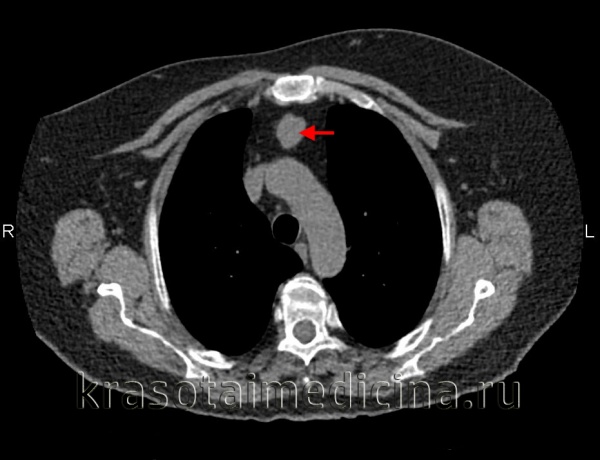

(б) Женщина 33лет, которой была выполнена КТА по поводу тромбоэмболии легочной артерии.

При сканировании в правой паравертебральной области случайно было выявлено мягкотканное объемное образование, гетерогенно накапливающее контрастное вещество.

Также было обнаружено расширение межпозвонкового отверстия на уровне позвонка Th8 и распространение опухоли в спинномозговой канал. При биопсии под ультразвуковым контролем был подтвержден диагноз шванномы.